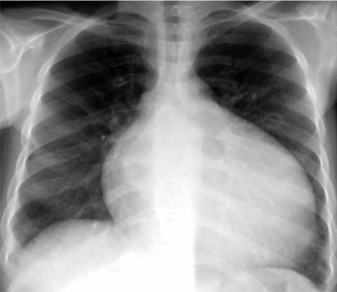

Homem de 59 anos de idade apresenta dispneia há cerca de 1 ano, inicialmente, aos grandes esforços, evoluindo para moderados e pequenos esforços. Exame físico: PA: 112 x 88 mmHg, FC: 112 bpm e FR: 16 ipm; ausculta pulmonar com crepitações em 1/3 de ambos os pulmões. radiografia realizada é mostrada a seguir.

Ao exame físico, a alteração que, mais provavelmente, deve ser encontrada é